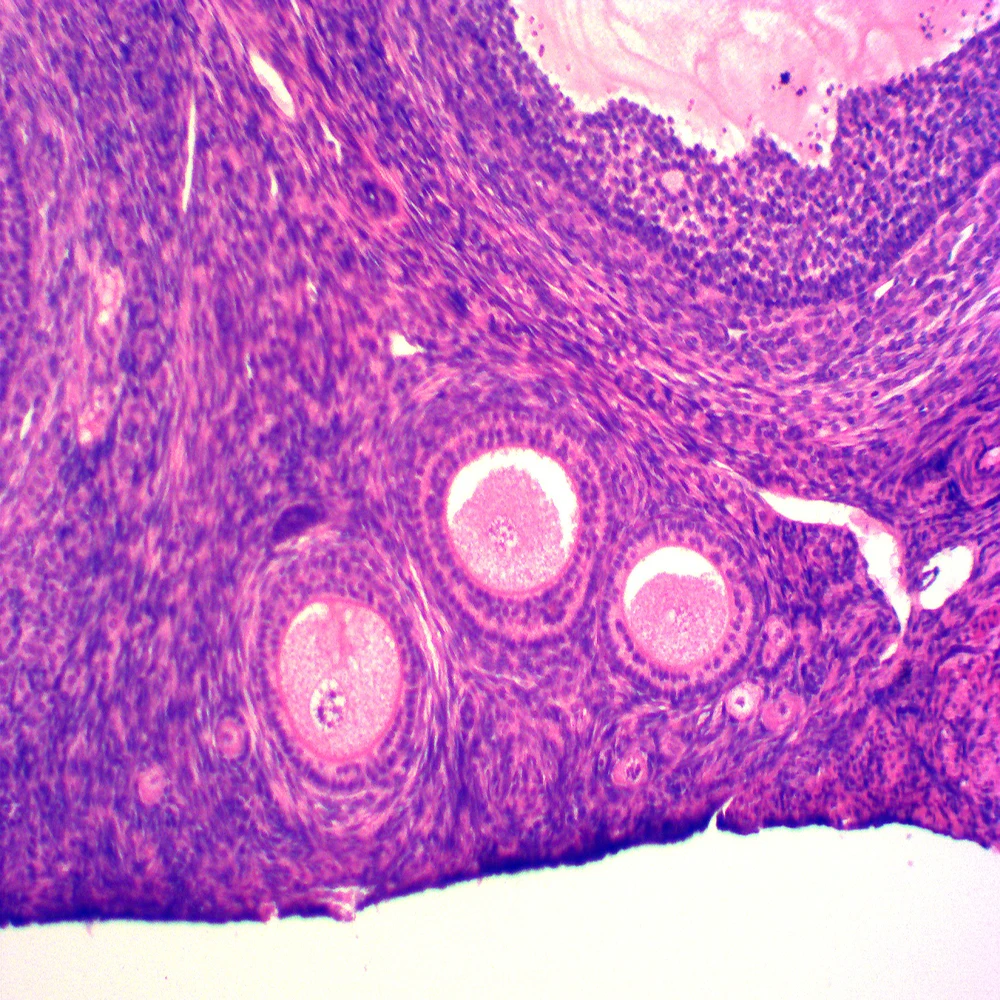

Гистологические изображения фолликулярной кисты яичника